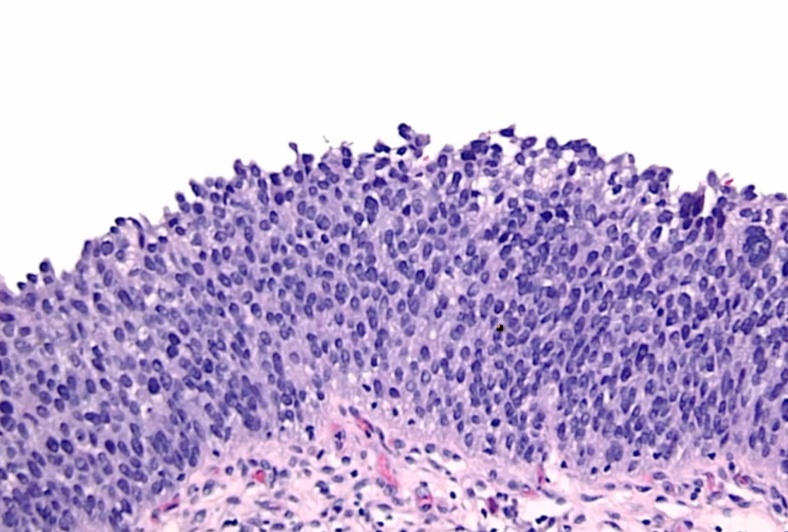

Transitional Cell Carcinoma

flat pathway: high grade flat tumor then invades. Early p53 mutation

papillary: low grade papillary tumor that progress to high grade and then invade. Not association with p53